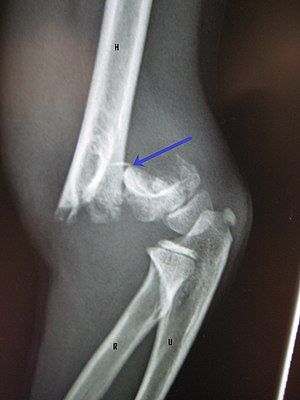

Supracondylar Fracture of the Humerus is a common elbow injury, especially in children. It occurs just above the elbow joint and can remarkably affect arm function if not managed properly.Early diagnosis and timely physiotherapy are crucial for optimal recovery.

Investigation

- X-ray of the elbow (anteroposterior and lateral views)

- Assessment of bone alignment and fracture displacement